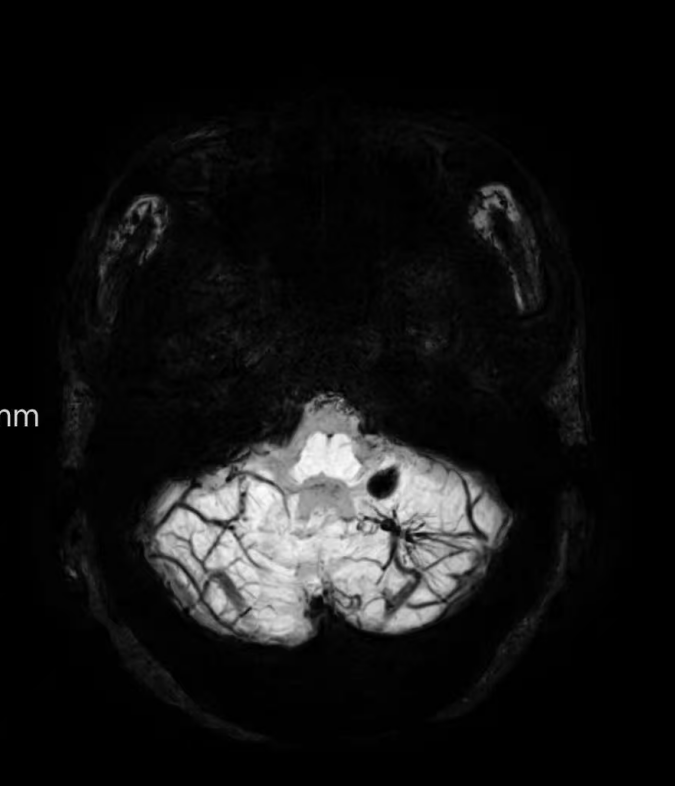

臨床中遇到一位患者,中年女性,反復(fù)出現(xiàn)頭痛,時(shí)輕時(shí)重,常規(guī)CT及磁共振檢查無(wú)明顯異常發(fā)現(xiàn),最后建議加做一個(gè)磁共振磁敏感加權(quán)成像(SWI),結(jié)果發(fā)現(xiàn)是左側(cè)小腦發(fā)育性靜脈畸形(DVA),SWI清晰顯示畸形的靜脈及周?chē)F血黃素沉積;如下圖。這正是她頭痛的原因。

①診斷靜脈畸形:SWI能高精度地顯示發(fā)育性靜脈畸形——一種常見(jiàn)的腦血管畸形。在SWI上,發(fā)育性靜脈畸形會(huì)呈現(xiàn)典型的“海蛇頭”或“水母頭”征,即一堆細(xì)小的髓靜脈匯入一支粗大的引流靜脈。